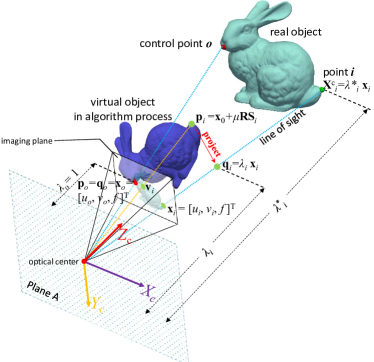

PP methods, which aim to estimate the position and orientation of a calibrated camera from known matches between 3D object points and their 2D image projections, have been widely used in SLAM systems for camera motion estimation. We propose to modify and improve our previous R1PPP work [9] to handle the problem of small number of matching inliers in the task of tissue surface reconstruction. In this section, we first briefly introduce the original version of R1PPP and then introduce our modification.

R1PPP is based on the standard pin-hole camera model, which is

| (5) |

where is the camera focal length, is the image homogeneous coordinate in pixels, and is the real-world coordinate with respect to the camera frame. Hence, we have

| (6) |

where is the normalized depth of point .

The relationship between the camera and world frame coordinate of point is

| (7) |

where is the rotation matrix and is the translation vector. and are the variables that need to be estimated in the PP problem. Selecting a point as the control point, we have

| (8) |

| (9) |

| (10) |

where and is the scale factor. We have

| (11) |

which suggests that can be computed from and .

The geometrical relationships of R1PPP is shown in Fig. 5. R1PPP combines a re-weighting strategy and the 1-point RANSAC framework to reduce the effects of outliers. The 1-point RANSAC framework randomly selects one match as the control point and then alternatively update , and to minimize the cost function